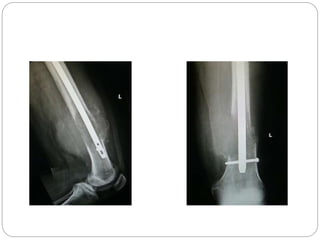

This document discusses 8 oncology cases. Case 1 involves a 40-year old female with right knee pain. Case 2 is a 28-year old male with a left subtrochantric fracture from a MVA who is now experiencing increasing left knee pain and swelling. Biopsy results showed high-grade osteosarcoma. Case 3 is a 30-year old female with breast cancer and bone metastases causing bilateral hip pain.